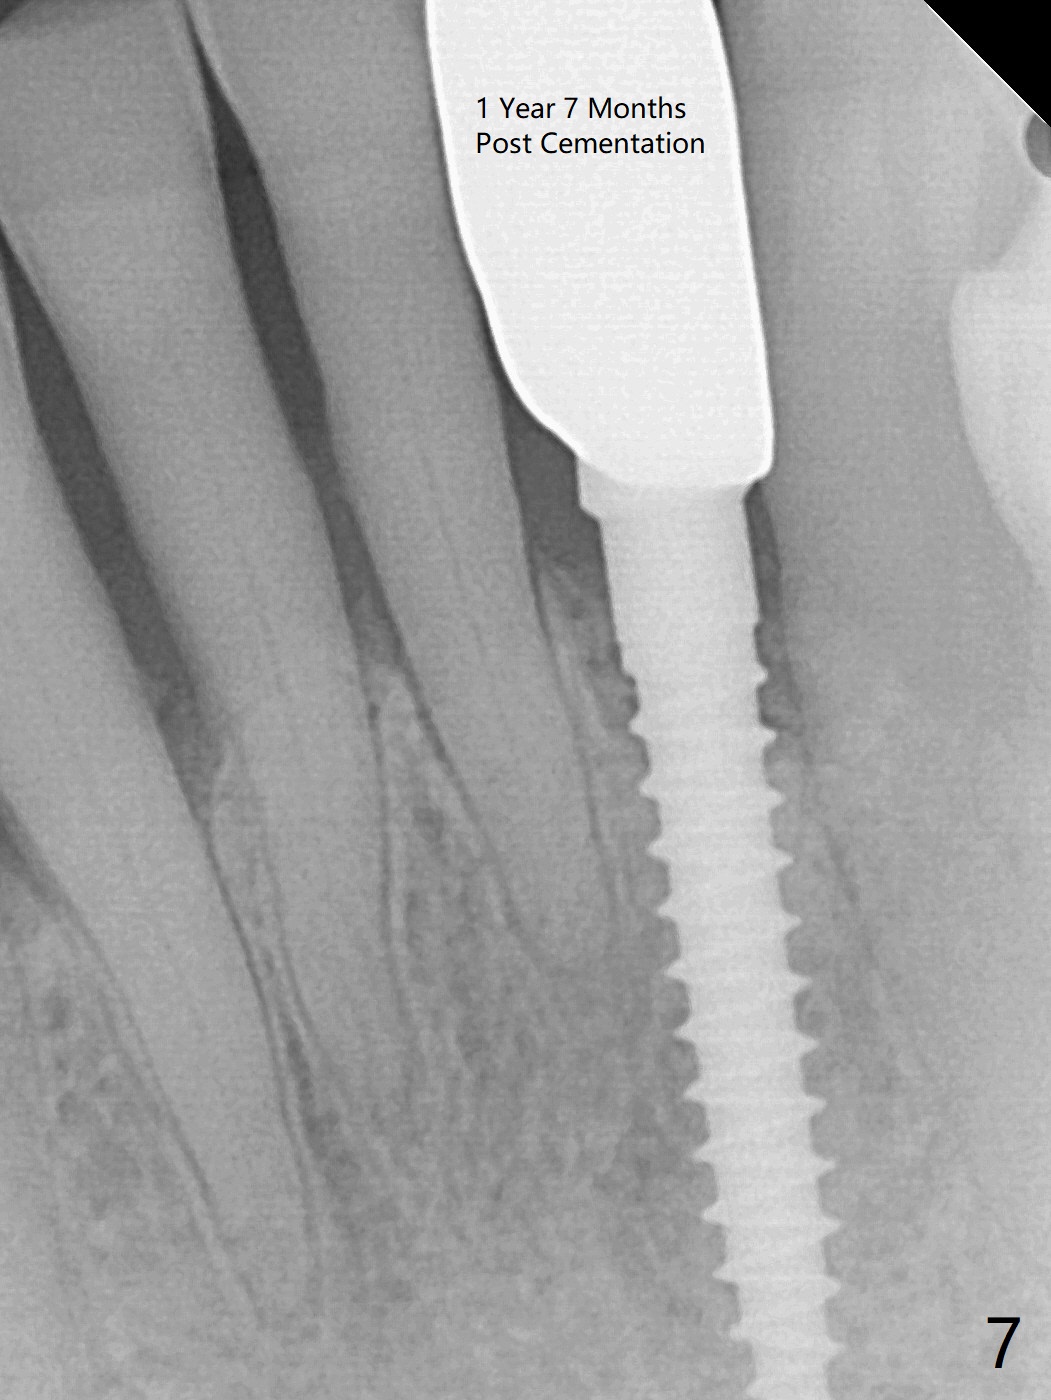

The tooth #23 is going to be extracted because the patient cannot masticate normally with mobility (Fit.1). The gingival depth is measured 2-4 mm after extraction. The 1st intraop PA taken with 1.2 mm drill for 16 mm shows the mesiodistal width is 5.11 mm (Fig.2); a 2.5x14(2) mm 1-piece implant is placed with >35 Ncm (Fig.3 with allograft placed). Following abutment preparation, an immediate provisional is fabricated to close the socket (Fig.4 P). There is no bone loss (Fig.5) or gingival inflammation (Fig.6 after reprep) 3 months postop. The narrow implant (2.5 or 2.0 mm) is indicated in the narrow edentulous space. The distal crest seems to be reduced in density and lower in height 1 year 7 months (Fig.7) and 1 year 11 months (Fig.8) post cementation. The severity does not worsen probably related to use of water pik. The crown looks bulky probably due to too large the abutment and too buccal placement of the implant (Fig.9, 10, as compared to Fig.1). A 2 mm implant may help?